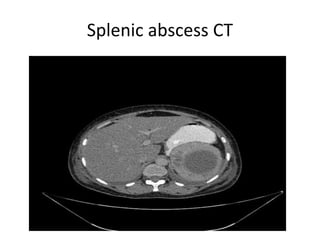

1. Splenic abscess: They are rarely seen in

spleen. May be solitary or multiple.

• X-ray: Gas transradiancy is seen i.e. a fluid

level is seen within the splenic mass in erect

radiograph. It is rarely seen but is enough to

make a doagnosis.

• CT scan: They appear similar to infarcts and

hematomas i.e. centrally low density lesions

(20-40 HU ) within splenic parenchyma. .

Minimal peripheral contrast enhancement

may be present when a capsule has developed

Splenic abscess CT